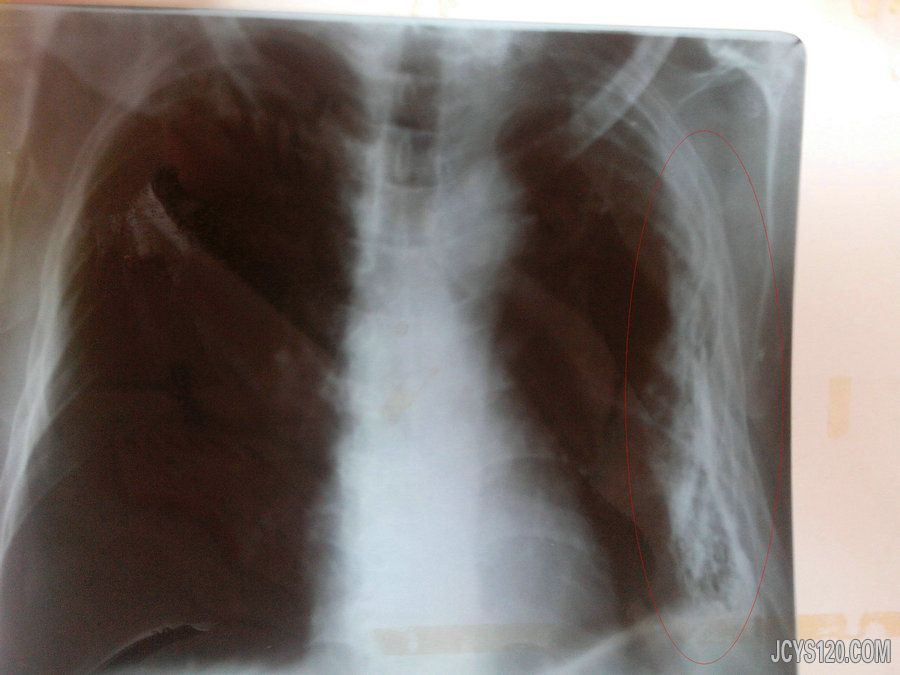

患者80岁,以肢体活动欠灵活诊断为脑梗塞就诊,询问病史时患者自述右侧胸痛,查体平右侧乳头处压痛明显,慢支、肺气肿病史40余年,给予胸片检查如下: 阅读全文>